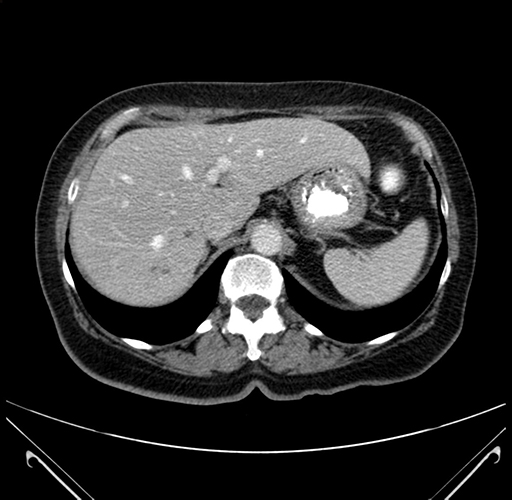

Pre-Chemo: Axial Venous

Axial Venous

Imaging analysis

Based on your CT findings, which issue(s) would give reason for "planned slowing down moment(s)" in this case?

Considering a standard right hepatectomy procedure, what step(s) of the operation would you do differently in this case?